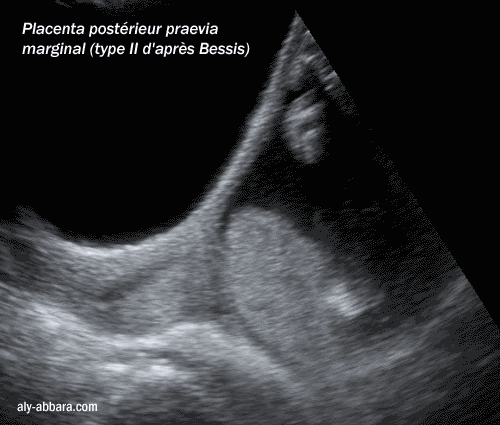

Placenta prævia, postérieur marginal à 33 semaines d'aménorrhée

(Type II selon BESSIS R, BRIGNON C, SCHNEIDER L. 1976)

Cette image montre l'insertion anormale du placenta ; il s'insère sur la paroi postérieure

du segment inférieur, et il atteint sans recouvrir l'orifice interne du col utérin